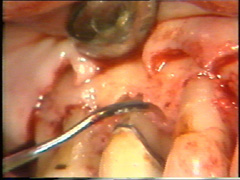

Se realiza una

segunda insición horizontal en el fondo de la bolsa para facilitar el levantamiento del tejido de

granulación

El levantamiento del tejido de

granulación se realiza en un tiempo y el procedimiento en sí es

exigente. Puede hacerse antes o después del levantamiento del colgajo.

El sangrado se controla bien y el tiempo de exposición del hueso

al medio bucal es reducido, cuando el tejido de granulación es

eliminado antes del levantamiento del colgajo.